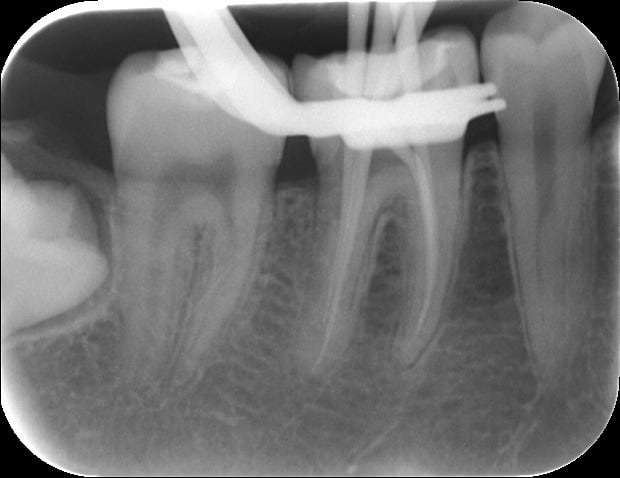

Voilà les radios apres obturation.

Il n'y a pas eu de fusée de gutta...ouf!

J'ai mis vraiment très très peu de ciment et en distal j'ai renforcé la dent avec un collage avec du composite flow. Et puis j'ai terminé avec un composite classique en occlusal.

La patiente est prévenu que l'avenir de cette dent est incertain mais ravie qu'on ai essayé de tout faire pour la sauver.

PS: désolé pour la dernière radio à l'envers...

Radio pré-op= furcation (concavité) très prononcé avec 2 racines distales distincts.